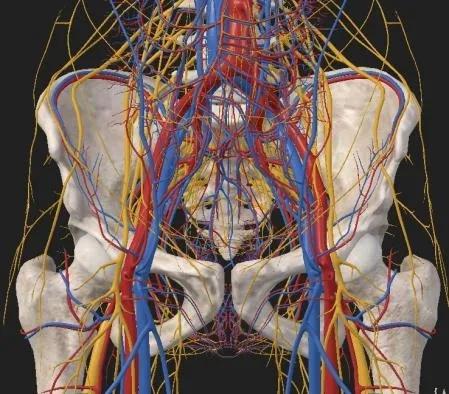

髋臼,作为连接躯干与下肢的“承重碗”,其解剖结构复杂、生物力学关键,直接决定着人体负重、行走与平衡功能。复杂髋臼骨折因其位置深在、骨折类型多变、毗邻重要神经血管结构,长期以来被视为创伤骨科领域最具挑战性的手术。

▲髋臼周围血管神经分布